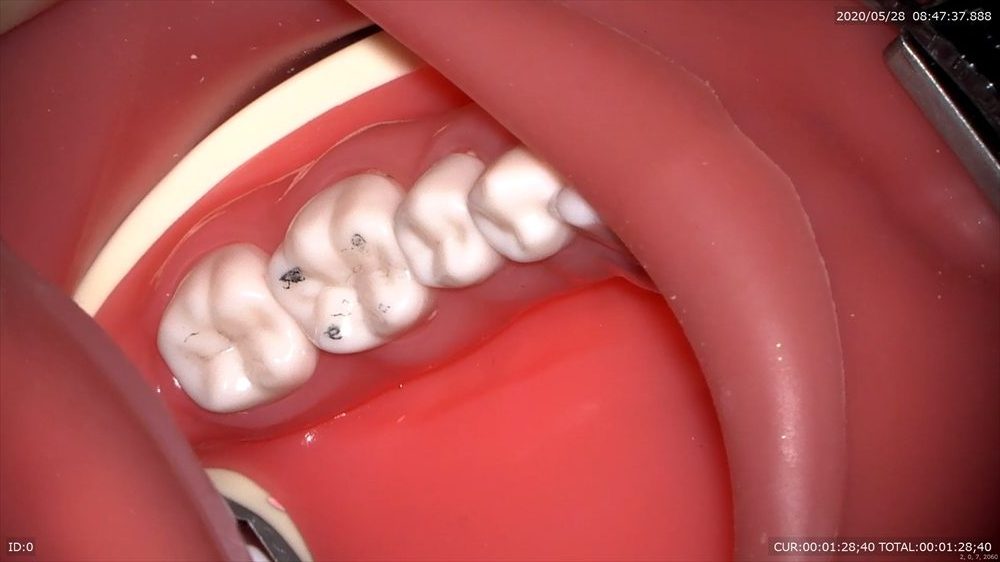

これは3倍率のマイクロスコープの映像。

3倍率では分かりにくかった黒点がこんなにも傷ついているのが分かると思います。